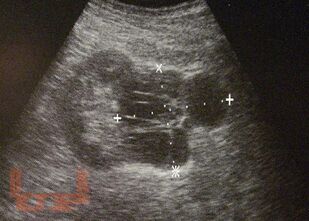

В учебном пособии отражены сведения, касающиеся, методики ультразвукового исследования и ультразвуковой семиотики опухолей почек и мочеточников. Особое внимание уделяется использованию метода в первичной, дифференциальной и уточняющей диагностике у онкоурологических пациентов.